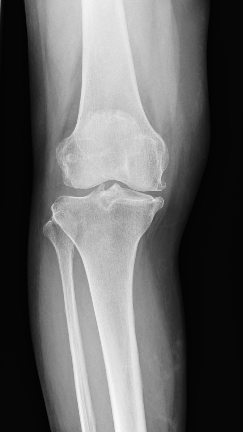

人工膝関節置換術とは?

変形性膝関節症や関節リウマチによる関節の変形によって、痛みや動きにくさなどで日常生活に影響が出てしまった場合に選択される手術方法です。

TKAは、変形した太ももの骨(大腿骨)とすねの骨(脛骨)の関節面を人工の関節に変える手術です。

変形の程度によって、人工膝関節単顆置換術(Unicompartmental Knee Arthroplasty 以下UKA)という手術方法があります。TKAは大腿骨と脛骨の関節面を全部人工関節に取り替えてしまうのに対し、UKAは大腿骨と脛骨のそれぞれ片側だけ(内側がほとんど)を交換する方法です。